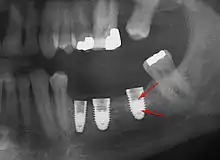

Long-term failures are due to either loss of bone around the tooth and/or gingiva due to peri-implantitis or a mechanical failure of the implant. Because there is no dental enamel on an implant, it does not fail due to cavities like natural teeth. While large-scale, long-term studies are scarce, several systematic reviews estimate the long-term (five to ten years) survival of dental implants at 93–98 percent depending on their clinical use.[1][2][3] During initial development of implant retained teeth, all crowns were attached to the teeth with screws, but more recent advancements have allowed placement of crowns on the abutments with dental cement (akin to placing a crown on a tooth). This has created the potential for cement, that escapes from under the crown during cementation to get caught in the gingiva and create a peri-implantitis (see picture below). While the complication can occur, there does not appear to be any additional peri-implantitis in cement-retained crowns compared to screw-retained crowns overall.[68] In compound implants (two stage implants), between the actual implant and the superstructure (abutment) are gaps and cavities into which bacteria can penetrate from the oral cavity. Later these bacteria will return into the adjacent tissue and can cause periimplantitis.